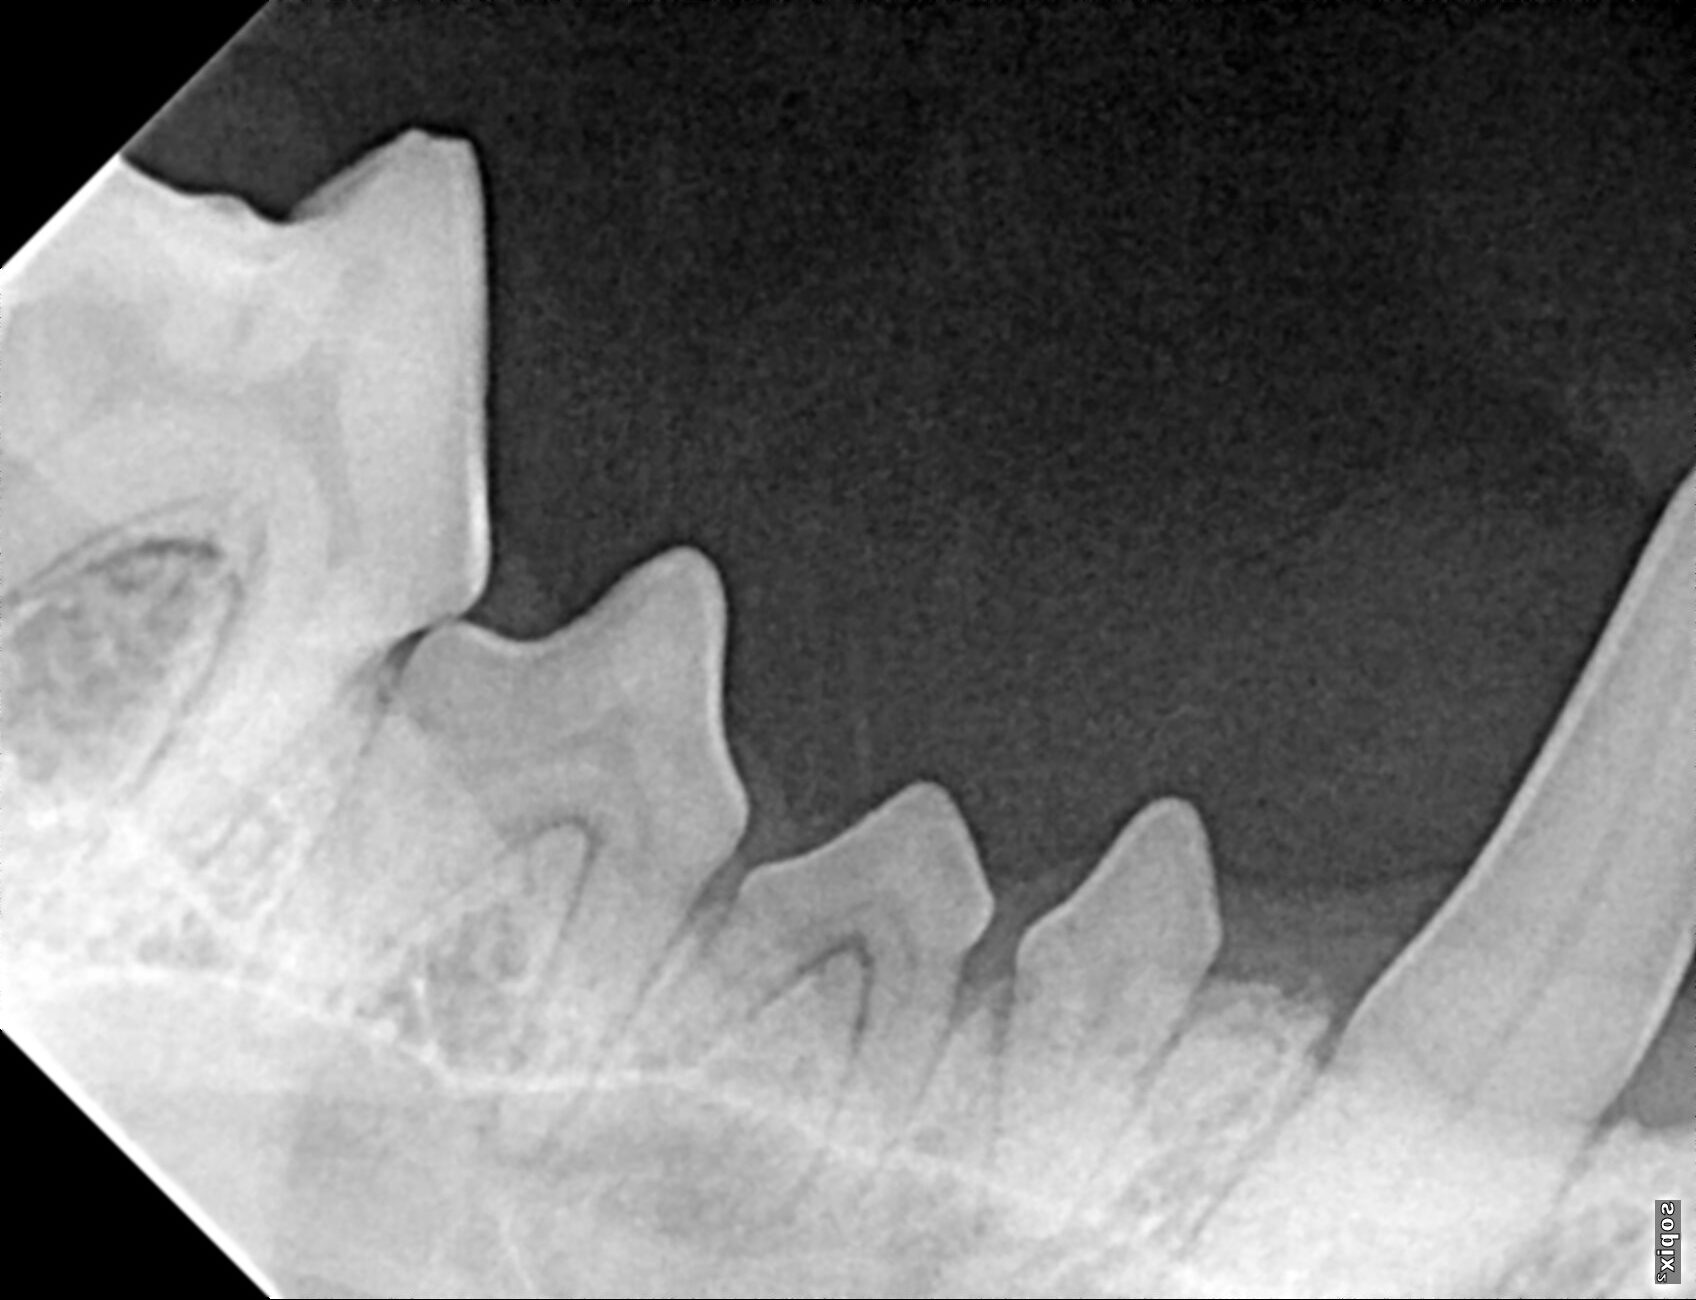

The prophylactic dental includes x-rays of all the teeth, ultrasonic scaling of the plaque and tartar from the teeth, polishing, and fluoride treatment. It is impossible to determine the full extent of dentistry your pet needs until they are under anesthesia and we can examine each tooth individually, but we can give an estimate of your pets dental status and needs during your routine exam.